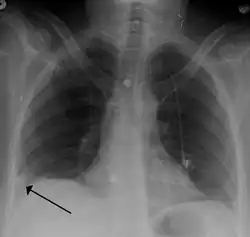

• Chest X-rays are often done on people with shortness of breath to help rule out other causes, such as congestive heart failure and rib fracture. Chest X-rays in PE are rarely normal,[70] but usually lack signs that suggest the diagnosis of PE (for example, Westermark sign, Hampton's hump).

A Hampton hump in a person with a right lower lobe pulmonary embolism